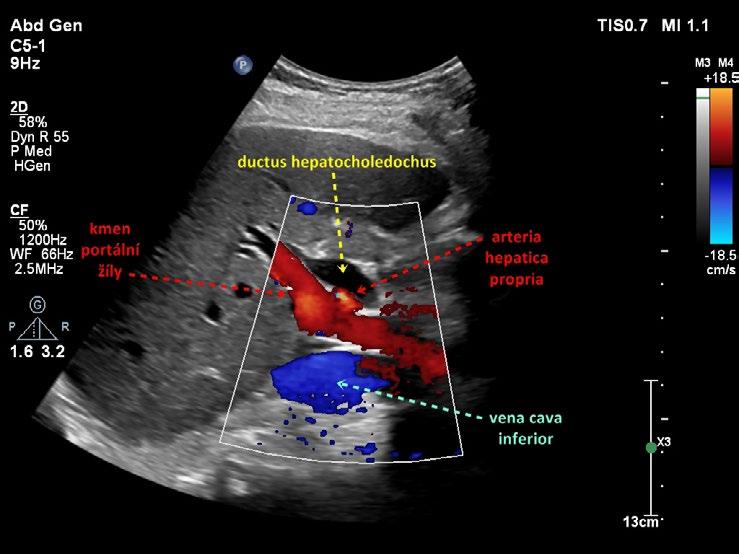

Obr. 1.24 Intrapankreatická část ductus hepatocholedochus

Obr. 1.26 Intrapankreatická část ductus hepatocholedochus podélně